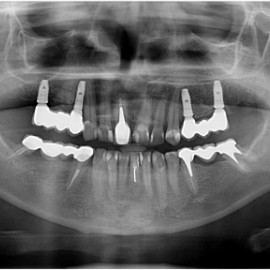

Implantacja natychmiastowa. Zęby paradontyczne. Usuniete zgodnie z popularną obecnie na zachodzie techniką: usuń zęby zanim zaniknie kość. Wynikiem takiego postępowania jest mniejsza trauma dla pacjenta i krótszy okres trwania rehabilitacji protetycznej, niższe całkowite koszty leczenia. Ale jednocześnie więcej implantów i mniej własnych zębów. W długotrwałym okresie obserwacji takie podejście daje dobre wyniki.

Pacjent z długą historią leczenia implantologicznego. Pierwsze implanty w pozycjach 23, 24 miał wkręcane w Warszawie przed 25 laty. Implant w pozycji górnego prawego kła ma agresywny gwint, ponieważ bezpośrednio po implantacji był obciążony (immediate loading) tymczasowym atachmentem ball abutmentv do stabilizacji tymczasowej protezy ruchomej. Kość szczęki regenerowana i odbudowywana etapami w całym górnym prawym kwadrancie. Pacjent planuje uzupełnić brakujące zęby 25, 26.

Pacjentka po ekstrakcji kilku zębów, z implantacją natychmiastową, odroczoną. Zdjęcie pantomograficzne wykonano pięć lat po implantacji. Widoczna stabilna sytuacja kostna i dziąsłowa.